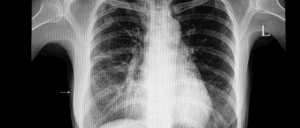

RSウイルスワクチン・肺炎球菌ワクチン

RSウイルスは小児で有名ですが、高齢者においても重症化しやすい感染症であることをご存じでしょうか。また、肺炎球菌も高齢者の肺炎の原因で最も多く、脳や全身に移行し、重症化しやすいことが知られています。現在、これらの肺炎予防ワクチンがあり、65歳以上の方へ予防接種が推奨されています。

RSVワクチンはインフルエンザワクチンよりも認知症予防効果があるという報告8が、また肺炎球菌ワクチンについても30%10-60%11のリスク減少が報告されています。